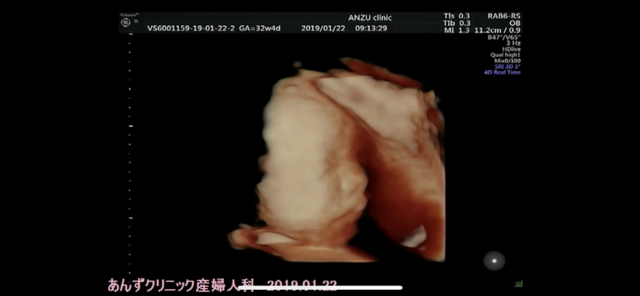

32週4日(32w4d・男の子)|ループ さん(32歳)

エコー写真撮影時のエピソード:

3Dを撮っていただいた時のもので、横顔の上、手で顔を隠してしまっているところです。産院で初めて女医さんに診てもらって、上の子と一緒にエコーを見ていたら、「お兄ちゃんになるんだよ~。」とたくさん声をかけてもらっていました。

上の子は初めて見た女医さんに若干人見知りをしていたようで、うんともすんともいわなかったのが見ていて面白かったです。